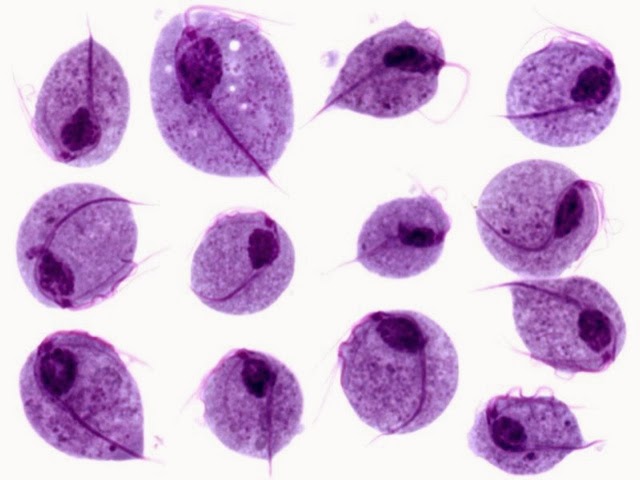

Gynekologen hittade en förändring i livmoderhalsen som han tog en biopsi ifrån. Hade lite små infall av dödsångest när jag låg där. Dessutom har jag någon slags pågående infektion (könssjukdom?) i underlivet som han såg eftersom det var vita blodkroppar i sekretet. Så nu proppar vi i oss antibiotika av olika slag, både jag och mannen.

Har haft problem till och från i några år nu, men aldrig fått någon riktig hjälp. Fått antibiotika utskrivet och så har det gått över men kommit tillbaka efter ett tag.